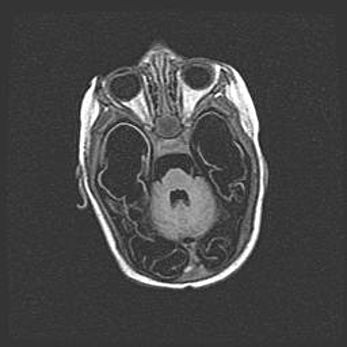

Ниже представлена  галерея МРТ снимков, полученных с применением LMT неонатальных матричных РЧ катушек. Также каждая группа МРТ снимков сопровождается информацией о пациенте (диагноз, возраст, вес, пол, срок гестации) и краткой сопроводительной расшифровкой диагноза.

Мальформация Денди-Уокера. Киста задней черепной ямки.

Агенезия мозолистого тела.

Возраст: 2,5 месяца

Вес: 2420 г

Пол: женский

Окружность головы: 37 см

Срок гестации: 32 недели

Мальформация Денди—Уокера — редкий вид патологии ЦНС, представляющий собой врожденный порок развития каудального отдела ствола и червя мозжечка, ведущий к неполному раскрытию срединной (Мажанди) и латеральных (Лушка) апертур IV желудочка мозга. Для этогно синдрома характерна триада симптомов: гипотрофия червя мозжечка и/или полушарий мозжечка, кисты задней черепной ямки, гидроцефалия различной степени. В 70% случаев порок сочетается и с другими аномалиями головного мозга, в частности с агенезией мозолистого тела.